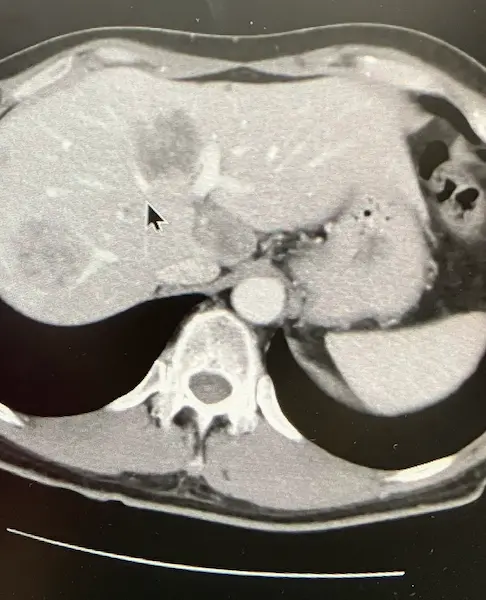

CT検査の結果は良好でした。 肝臓に転移したがんが、目に見えて小さくなっていたのです。

(腫瘍マーカー:178)

肝臓に転移したがんがさらに小さくなっていました。それを証明するかのように腫瘍マーカーも下がっていました。

(腫瘍マーカー16)

またCT画像では、がんが白く石灰化しているのが確認できました。腫瘍マーカーは7。ついにひと桁まで下がりました。

(腫瘍マーカー7)